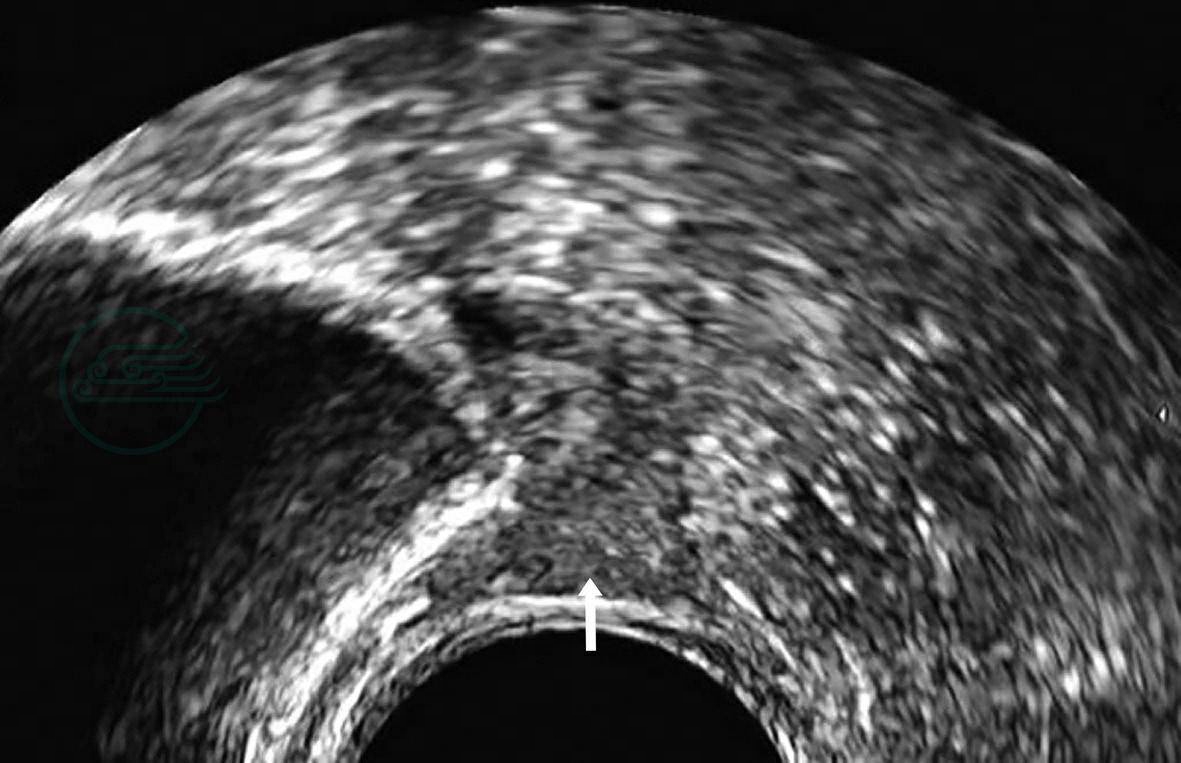

对始基子宫患者行腔内超声检查时,可在膀胱后方扫查到一等回声肌性结构(图1),宫体宫颈结构分界不清,且宫体与宫颈的比例失调,无宫腔线,或有宫腔线而无内膜回声。双侧始基子宫者,盆腔中央未见子宫声像,需在盆腔两侧仔细扫查,可在两侧卵巢旁查见两个等回声肌性结构(图2),回声均匀、边界清楚,与正常子宫肌层回声类似。

图1腔内超声始基子宫二维灰阶声像图

图示盆腔内一子宫样等回声肌性结构(箭)